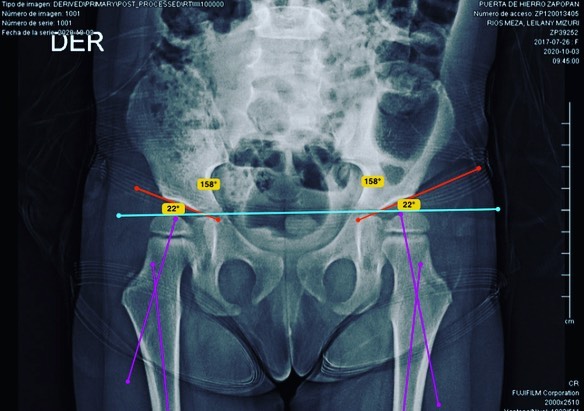

Quiero compartirles que doy de alta a mi pacientita Leilany, de 5 años. La operé por displasia de cadera causada por coxas valgas (región proximal del fémur muy vertical), que alteraba la morfología de su cadera y provocaba disfunción a largo plazo. Le realicé un tratamiento quirúrgico para corregir la deformidad y ahora está al 💯, lista para jugar y hacer travesuras. 🎉